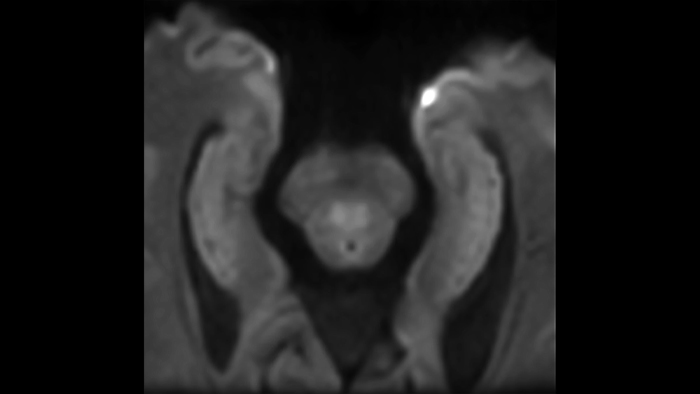

Zoom diffusion

Clinical application

Brain  Spine  Pelvis

Vanderbilt University, USA

2017